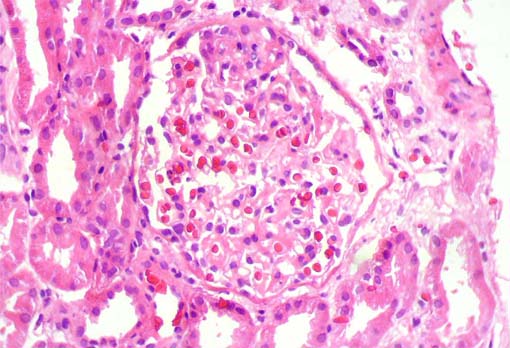

Figure 3.

H&E,

X400.